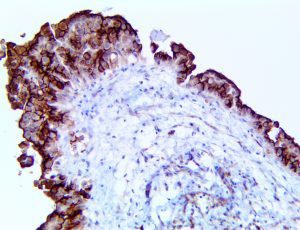

The first cytokines released are interleukin 1β (IL-1β) and tumor necrosis factor-α (TNF-α), which attract a variety of circulating white blood cells (WBCs) to the infection site, including neutrophils, monocytes, macrophages, and natural killer (NK) cells. This response, along with the antipathogenic chemicals released by these cells (i.e., complement), comprise the innate immune response. These cells directly attack the invading pathogen and also release additional cytokines, chief among them interleukin-1 and 6 (IL-6). IL-6 is essential for invoking the adaptive immune response, which calls T-cells, B-cells, and T helper (Th) cells to the infection site. IL-6 also stimulates further recruitment, proliferation and activation of macrophages.

This activation induces inflammatory monocytes to highly express IL-6, starting a localized and then systemic cascade effect that results in hyperproduction of IL-6, which accelerates the inflammatory process. Because IL-6 also increases vascular permeability, excessive levels cause blood vessels to become very leaky. This, along with clotting factors released from vascular endothelial cells, stimulates the coagulation cascade, resulting in microthrombosis (tiny clots), which leads to ischemia and tissue death of the kidney, intestines, heart, liver, brain and extremities.